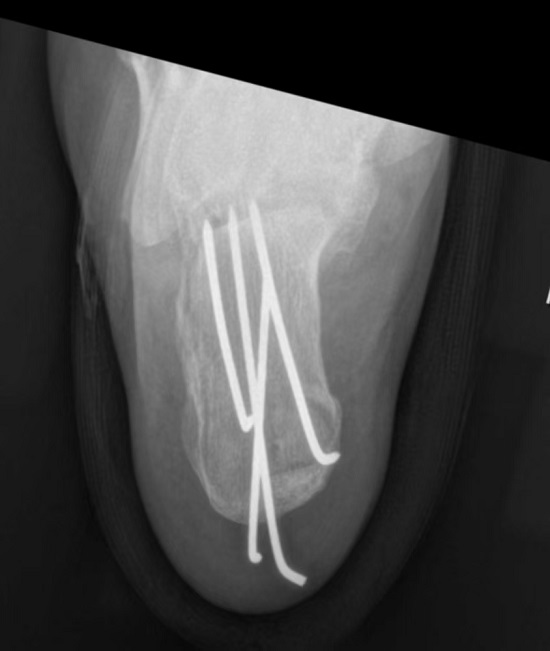

52岁的张先生下山时不慎从1米高处坠落,右足跟部严重摔伤,诊断为右跟骨粉碎性骨折(SandersⅡ型)。手足显微外科手术团队为其实施关节镜辅助下微创手术,通过精准复位与克氏针固定,术后疼痛较传统手术轻,切口一期愈合,未出现感染、皮肤坏死等并发症。术后4周复查,骨折愈合良好,拔除克氏针后开始逐步负重锻炼;术后10-12周已实现全负重,期间每4周一次的CT复查均显示骨质愈合正常。如今,张先生已完全恢复正常生活与工作,无任何不适困扰。

该技术借助关节镜的高清视野,通过微小切口即可完成骨折复位与固定:先以牵引器牵引、克氏针撬拨实现关节面精准复位,再用6-8 枚克氏针牢固固定跟骨,术中通过C臂透视实时确认复位效果与内固定位置,全程操作精细、安全可控。